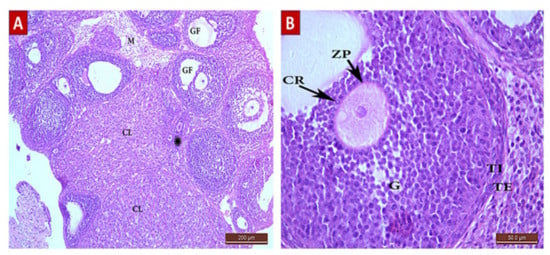

2.4.1. Hematoxylin and Eosin staining results

The Control Group (Group I, Figure 1, Figure 2, Figure 3 and Figure 4)